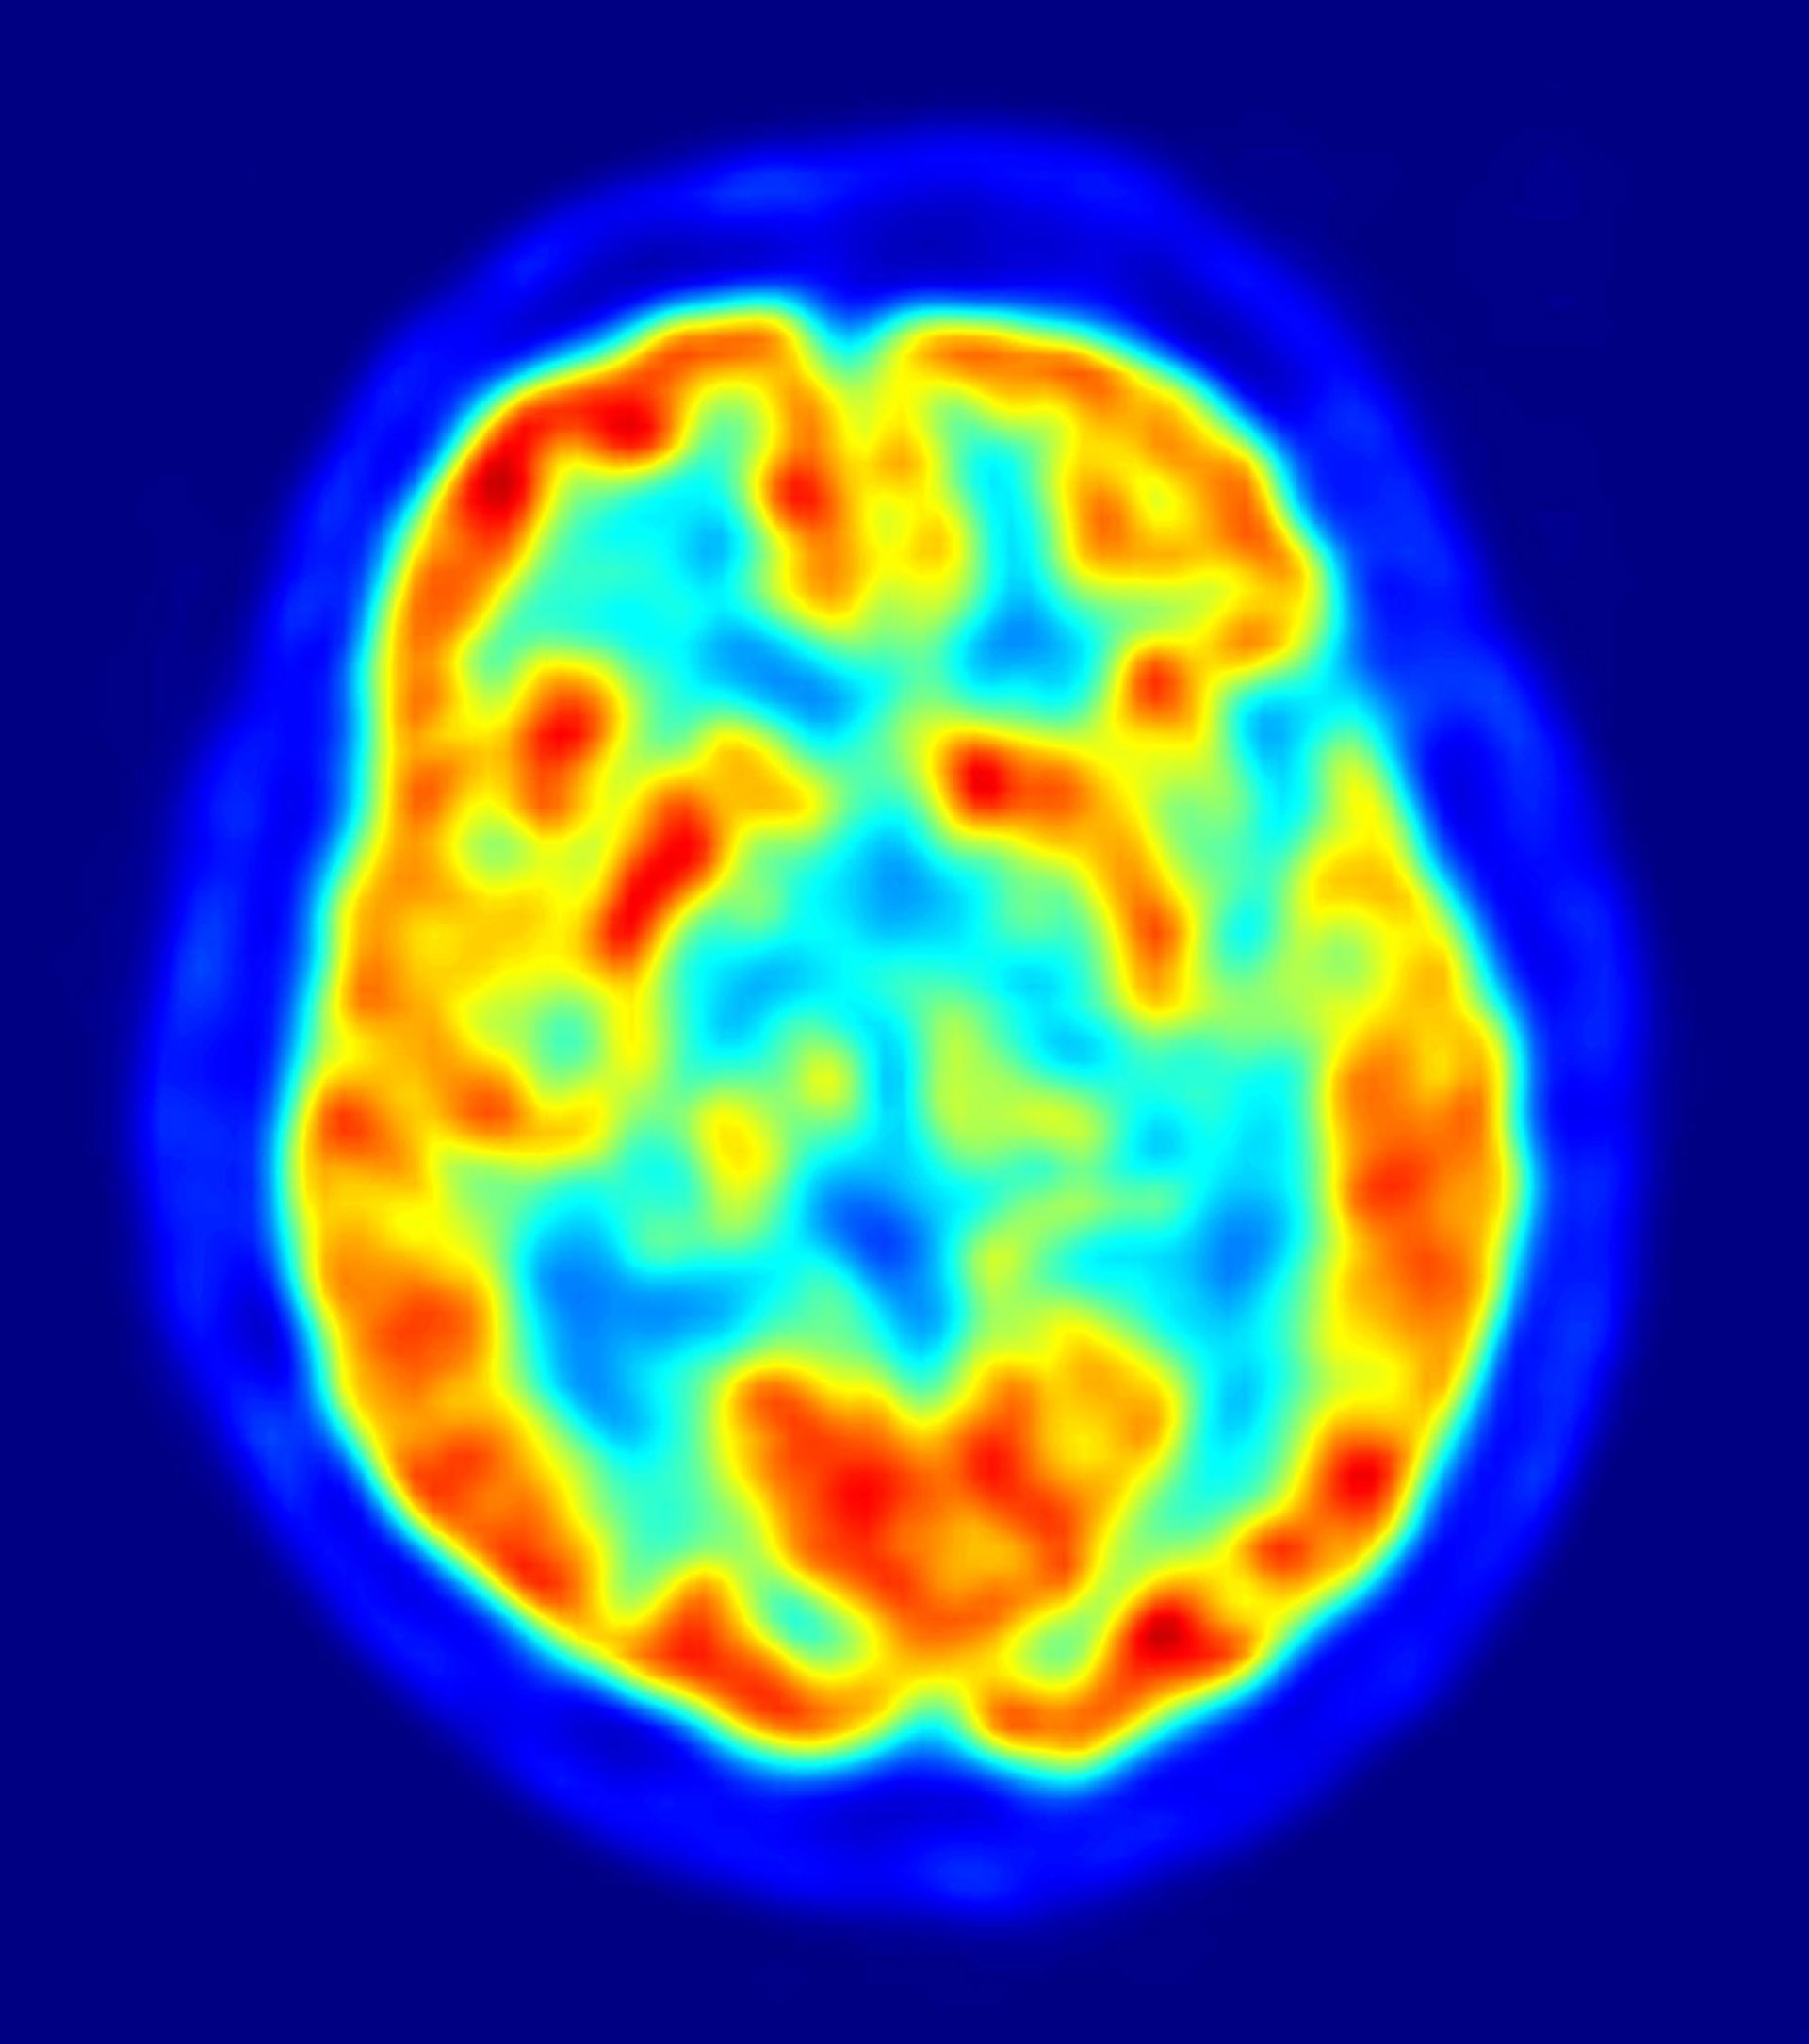

En un comunicado, sus responsables han explicado que "la barrera hematoencefálica (BHE) aísla al cerebro del resto del organismo y controla de forma selectiva las sustancias ajenas al sistema que deja pasar y las que no" y esta función protectora "choca" con la biomedicina porque supone "un obstáculo" que no permite concluir con éxito la entrega al cerebro de medicamentos necesarios en el tratamiento de enfermedades como el Alzheimer o el Parkinson.